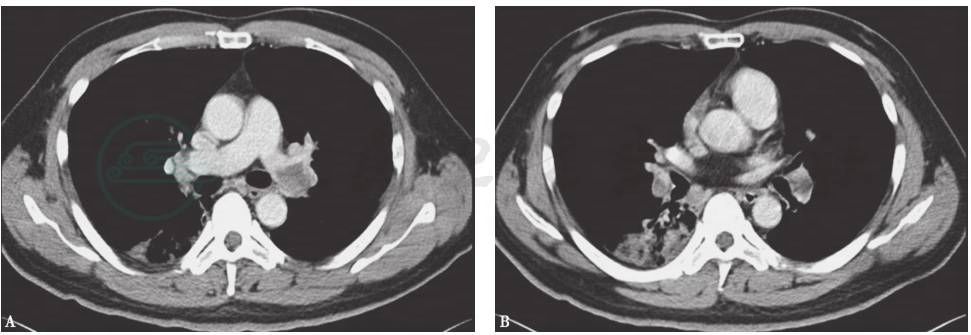

胸部CT(入院前1周,当地县医院):双下肺部分支气管轻度扩张并感染,并见右下肺索条影,双侧少量胸腔积液(图1)。

图1 胸部CT表现(入院前1周,当地县医院)

胸部CT显示双下肺部分支气管轻度扩张并感染,并见右下肺索条影(A),双侧少量胸腔积液(B)